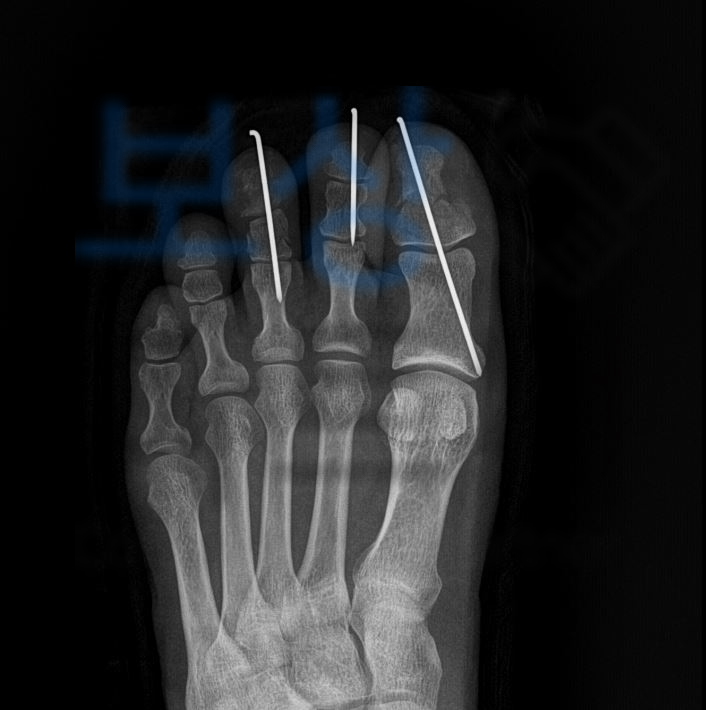

가운데발가락의 골절로 핀 고정술을 받으셔야 했습니다. 먼저 일하다 다친 사고이기에 의무보험인 산재보험에서 보상받을 수 있습니다. 의뢰인은 원무과의 도움으로 산재 최소 신청을 무사히 진행하셔서 요양급여 및 휴업급여를 지급받고 계셨는데요,

의뢰인은 골절된 부위에 핀 고정술을 하셔서 향후 발가락의 움직임 즉 운동범위 기능을 장해 진단을 받으셔야 했는데요,

엄지부터 중지발가락의 장해 14%